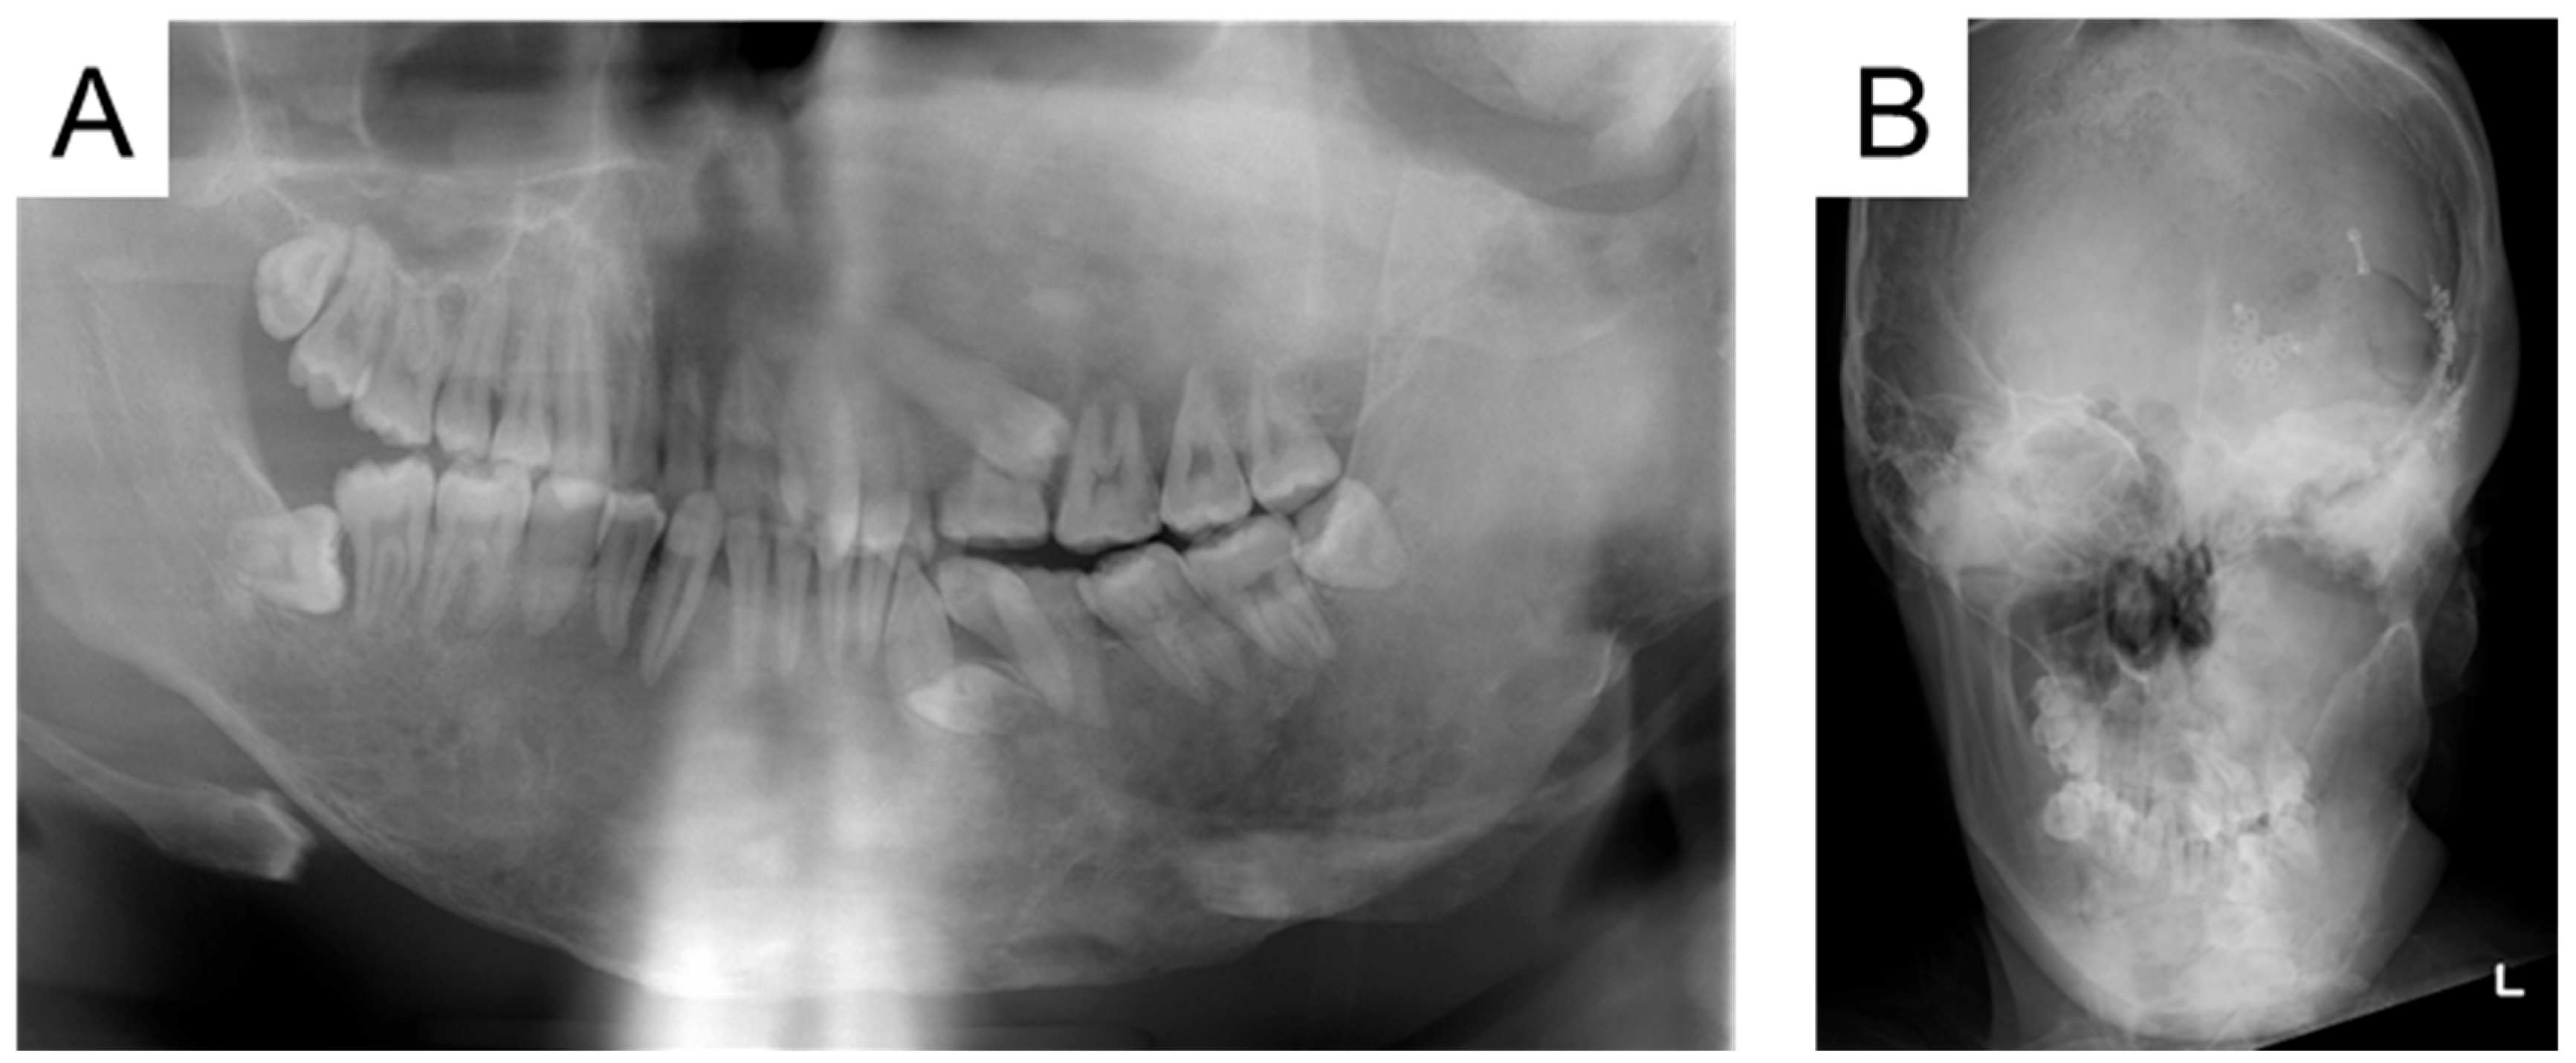

| 25 y 1 m | 9.11 | 20.85 |

| 27 y 4 m | 6.85 | 18.38 |

| 30 y 5 m | 4.86 | 14.38 |

| 24 y 10 m | Left mandibular primary second molar extraction |

| 30 y 3 m | Left mandibular primary canine extraction |